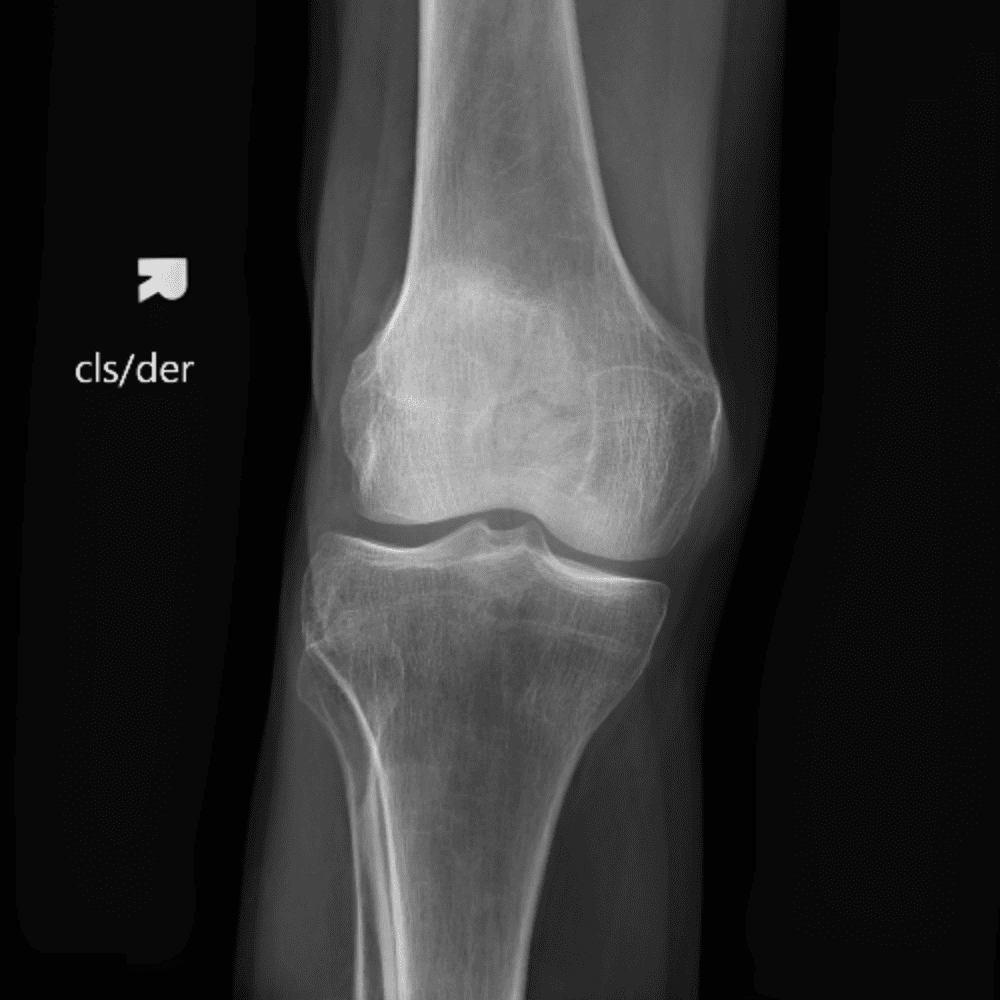

Simula o plantão incluindo casos sutis ou difíceis e alguns normais.